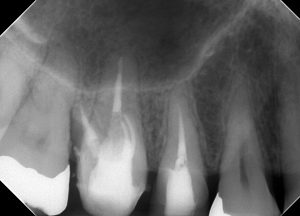

レントゲンを見てみよう。

(術前レントゲン、CT)

全ての根管に、根尖病変が存在する。

打診(+)、咬合痛(+)の状態であった。